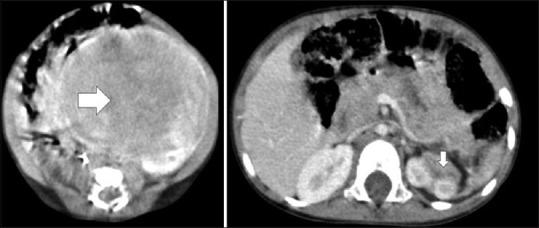

Among six, two each were adolescent and neonate, and one each was young infant and prenatal. Clinical presentation was variable; hypertensive retinopathy,[1] virilization[1] and bleeding diathesis,[1] antenatal suprarenal mass,[1] prenatal adrenal angiolipoma,[1] and spontaneous resolution of Stage III suprarenal mass.[1] Ultrasound and contrast-enhanced computed tomography revealed well-defined, heterogeneous adrenal mass. Size varied from 2 to 15 cm. Urinary metanephrine and serum testosterone were raised in adolescent hypertensive boys and virilized girls, respectively. Laparoscopy-assisted adrenalectomy was done in two and other four were managed conservatively. Histopathology of tumor revealed pheochromocytoma and borderline oncocytoma. Spontaneous resolution of adrenal mass had varied etiology; adrenal hemorrhagic lesion,[1] simple cyst,[1] neuroblastoma.[1] Follow-up varied from 3 months to 2 years. All patients were asymptomatic on last follow-up.

6例患者中,青少年和新生儿各2例,幼儿和产前诊断各1例。临床表现多样,包括高血压性视网膜病变[1]、男性化[1]和出血倾向[1]、产前肾上腺肿物[1]、产前肾上腺血管脂肪瘤[1]以及Ⅲ期肾上腺肿物自发消退[1]。超声和增强CT显示肾上腺肿物边界清晰、密度不均。大小从2厘米至15厘米不等。青少年高血压男孩和男性化女孩的尿间甲肾上腺素和血清睾酮分别升高。2例行腹腔镜辅助肾上腺切除术,另外4例采取保守治疗。肿瘤组织病理学检查显示为嗜铬细胞瘤和临界性嗜酸性细胞瘤。肾上腺肿物自发消退病因各异,包括肾上腺出血性病变[1]、单纯囊肿[1]、神经母细胞瘤[1]。随访时间从3个月至2年不等。末次随访时所有患者均无症状。